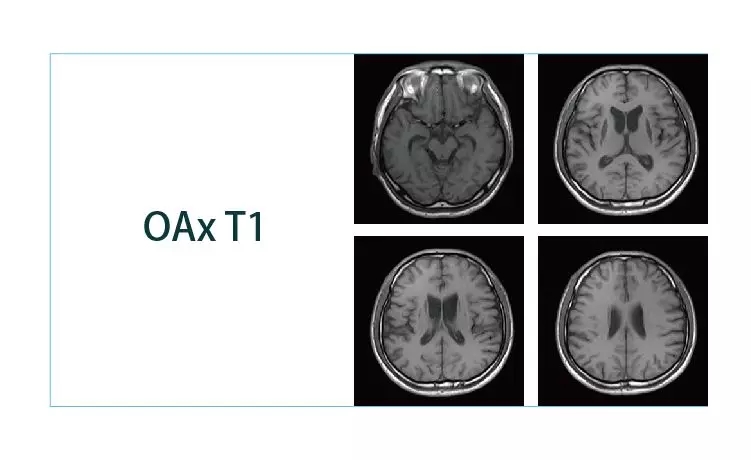

【朗润影像档案】20190111磁共振影像病例结果讨论